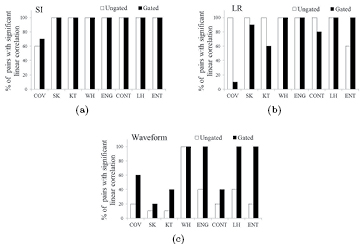

Our set-up permitted us to study the effect of the three main characteristics of respiratory movement on heterogeneity quantification (table 1): amplitude along SI, hysteresis and waveform. TF values derived from the G- and U-image were analyzed in terms of LCs for ten possible combinations of the five movements applied to the phantoms in each study. The results are shown in figure 8. Different behaviors were observed depending on the TF and on the characteristic of the movement considered. For a given waveform, increasing the amplitude along SI did not translate to significant differences between TF response on the G- and U- image. Hysteresis did not compromise variability on the U-image, but for G-quantification by first order TF (FOS), poorer variability was observed. It could be due to higher sensitivity of FOS to poorer G-frame statistics implied by these two-path movements. The waveform showed the most significant impact on TF variability. For different waveforms, U-image quantification had poor correlation for TF, both first and second order. This effect was minimized using the G-image. Overall, an ideal performance, i.e. significant LC for all pairs of movements (30/30), was obtained for WH on the U-image and WH, ENG, LH and ENT on the G-image.

Figure 8. Percentage of combined pairs of movements ( pairs) with significant LC for TFs. The characteristics of movement studied were: variation in SI amplitude (a), in LR amplitude (b) and in the waveform (c).

pairs) with significant LC for TFs. The characteristics of movement studied were: variation in SI amplitude (a), in LR amplitude (b) and in the waveform (c).